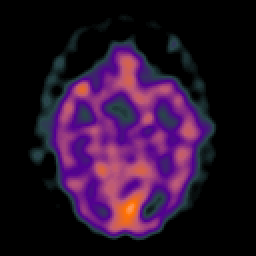

Glioma overlay -- Slice #11

[Home][Help][Clinical] Slice 11